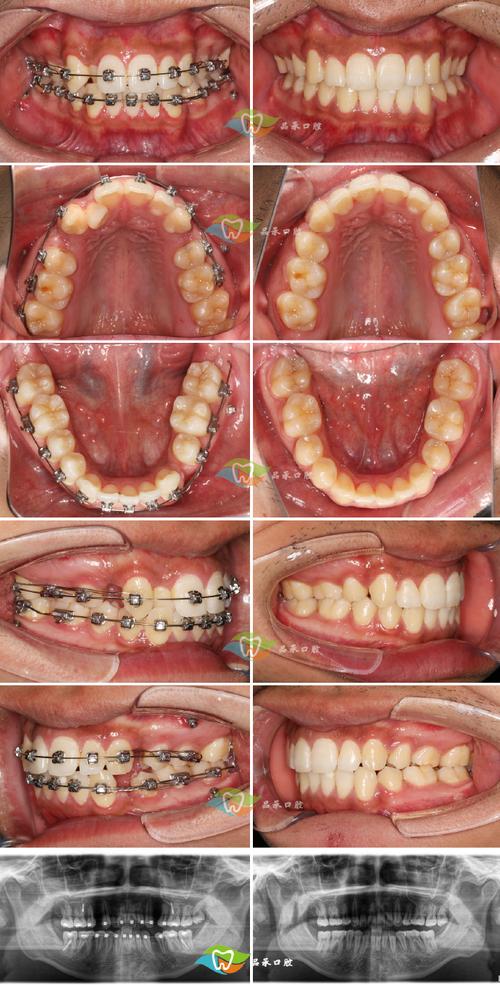

- 影像学检查: 通常需要拍摄全景片(曲面断层片)和根尖片,观察牙根位置、形态、牙槽骨状况,排除根粘连、骨皮质粘连等可能阻碍移动的因素,有时可能需要拍摄CBCT(锥形束CT)进行更精确的三维评估。

(图片来源网络,侵删) - 处理牙齿本身问题: